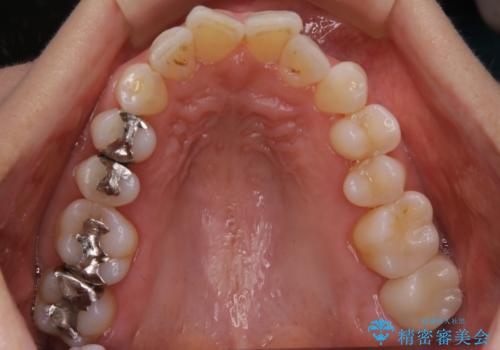

- 一番奥の歯に違和感がありご来院頂いた患者様です。

診断の結果、一番奥の歯は失活していたため精密根管治療から治療介入となりました。奥から2番目の歯にも大きな虫歯が認められたため、セラミックインレーによる補綴治療を行いました。 精密根管治療は患者様のご希望により、福本院長に行っていただきました。

今後は他の銀歯のやり替えも順次行っていくこととなりました。